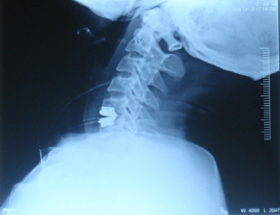

DIAGNOSIS OF SPINE TUMORS

Accurate and early diagnosis is essential.

Tests include:

MRI Scan

Best for detecting tumors and nerve involvementCT Scan

Helps assess bone destructionBiopsy

Confirms the type of tumor (benign or malignant)Blood tests

To evaluate overall health and detect underlying causes